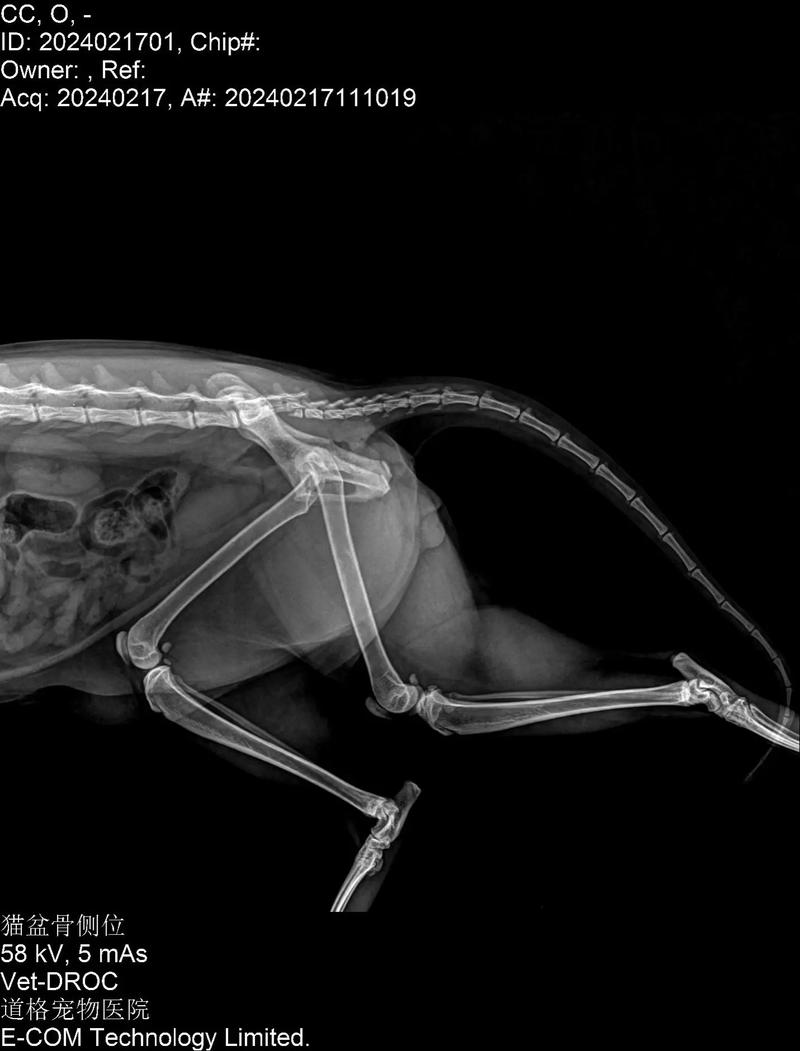

如果发现猫咪尾巴有一段像骨折一样,很可能是因为尾巴骨头出现了断裂。 建议主人及时带猫咪去医院进行X光检查,以确诊尾巴的状况。 正常情况下,猫咪的尾巴由多块骨头组成,虽然灵活但不会弯曲。 如果尾巴出现弯曲,可能是由于尾巴部位的骨头断裂所致。 幼猫可能不会表现出强烈的疼痛感,尤其是在出生后不久。

猫咪尾巴有一段像骨折一样很可能是骨头出现断裂引起的,建议主人及时带猫咪去医院拍片检查。正常的猫咪尾巴是由很多块骨头组成的,虽然很柔软但不会有折,如果发现有折说明猫咪尾巴在弯折处的骨头很可能出现了断裂,这种情况需要拍摄X光做最后的确诊。

如果发现猫咪尾巴有一段类似骨折的状况,很可能是因为尾巴的骨头出现了断裂。 应该及时带猫咪去宠物医院进行X光检查,以确诊尾巴的状况。 猫咪的尾巴由多块骨头构成,虽然灵活但不易折断。若出现折断现象,可能是骨头断裂所致。